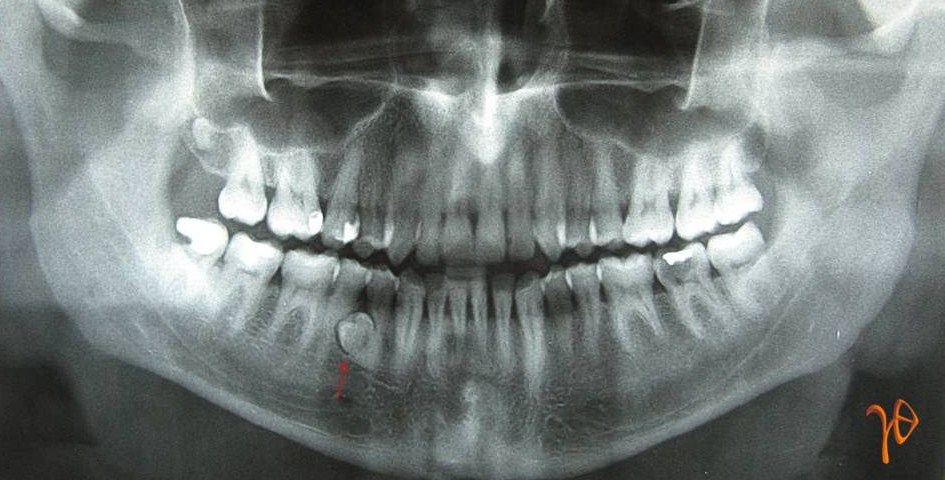

Εικ. 1: Πανοραμική ακτινογραφία του ασθενή στην οποία απεικονίζεται ο υπεράριθμος προγόμφιος (διακεκομένο βέλος). Ο ασθενής είχε υποβληθεί σε εξαγωγή του #14 για ορθοδοντικούς λόγους (διευθέτηση του #13 στο οδοντικό τόξο). Υποψία ακρορριζικής αλλοίωσης(συμπαγές βέλος ) στον #13(δοκιμασία ζωτικότητας θετική).